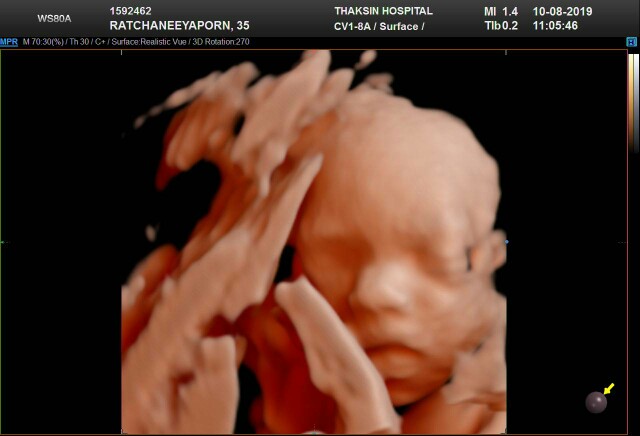

ซาวด์ตอน26wค่ะ